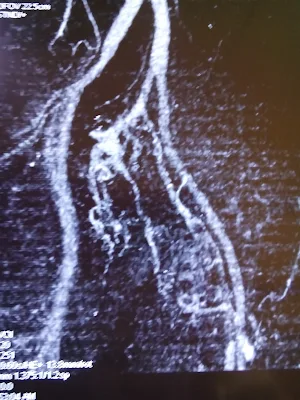

ANGIOTOMOGRAFIA IMAGENES DE TROMBOEMBOLIA PULMONAR CRÓNICA CON ATELECTASIA Y DERRAME PLEURAL EN PACIENTE CON TRES CUADROS PREVIOS DE TROMBOSIS VENOSA

LO QUE SE TOMA ANGIOTOMOGRAFIA CON LOS HALLAZGOS DE TROMBOEMBOLIA

PULMONAR CRÓNICA CON ATELECTASIA, DERRAME PULMONAR DERECHO,